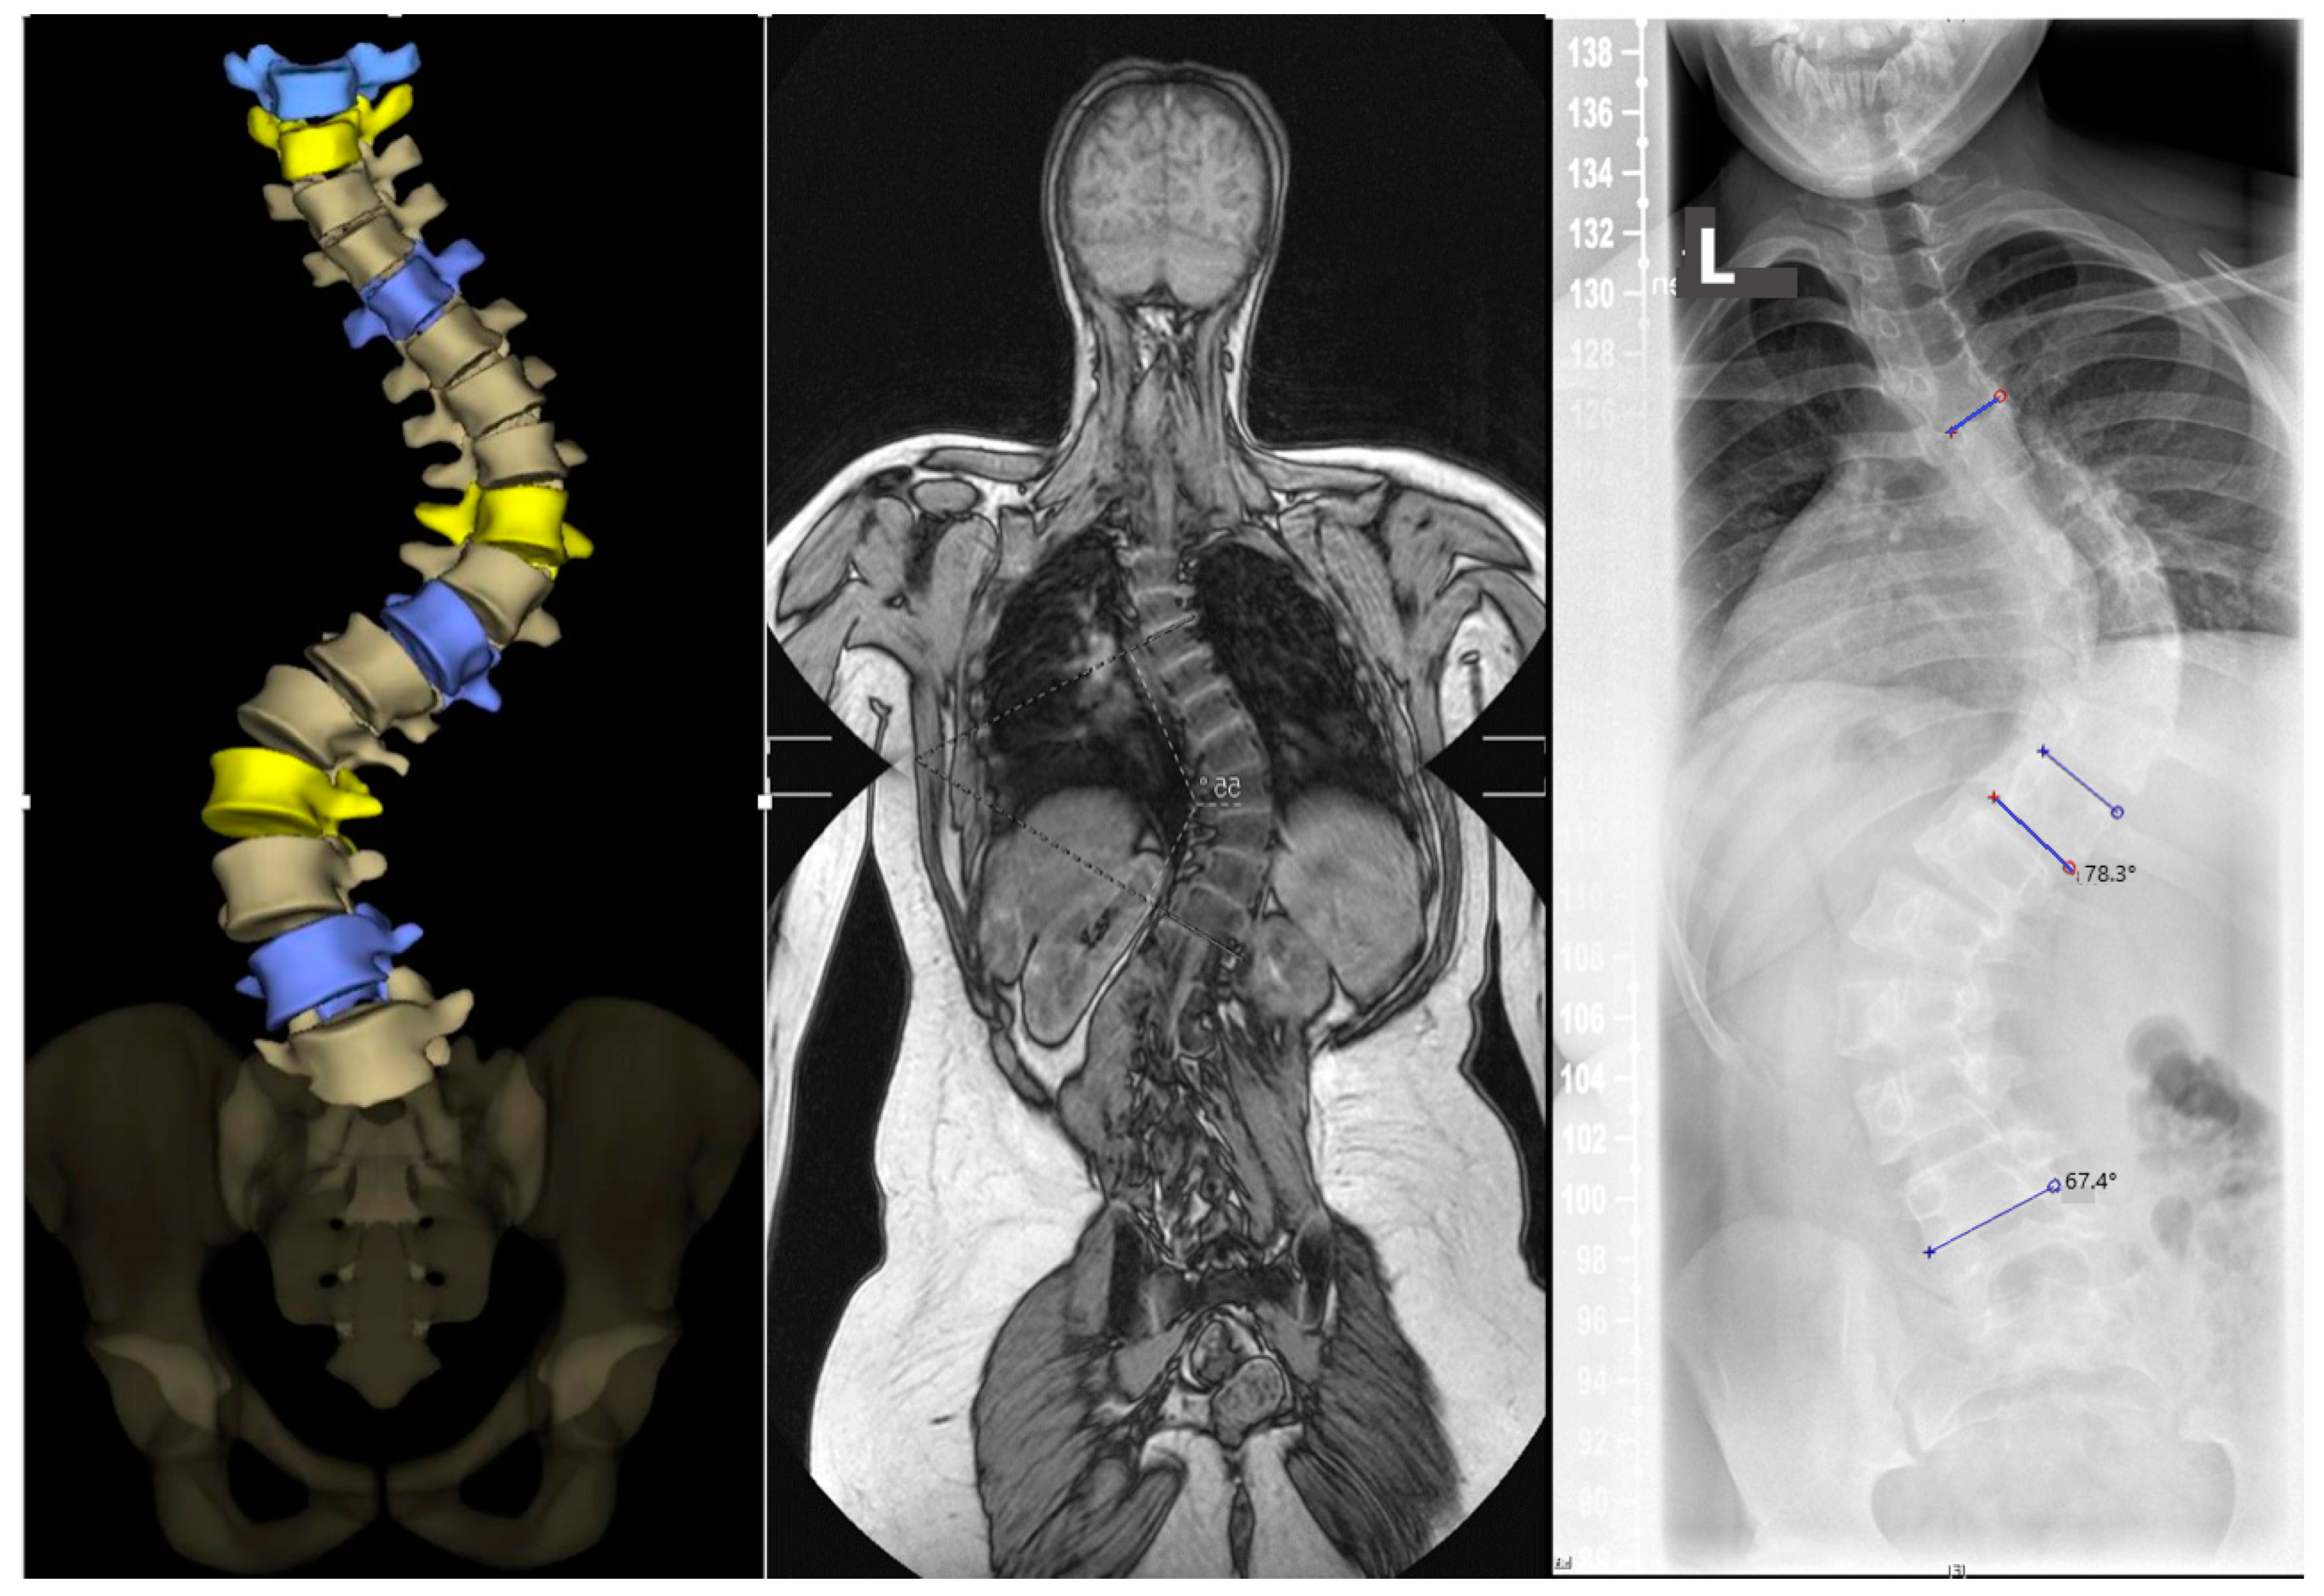

Figure 2.

From left to right: EOS, MRI scout image, whole-spine X-ray. (Left image) Coronary EOS view, with color-coded apical vertebrae in yellow and neutral vertebrae in purple. (Middle image) Coronary MRI image in T1W sequence for planning the thin-layer 3D sequences. (Right image) X-ray standing image for determining the Cobb angle. The blue lines are reference lines for calculating the angles. The upper line is for the thoracic curve, the two middle lines for the major curve and the lower line for the lumbar curve.